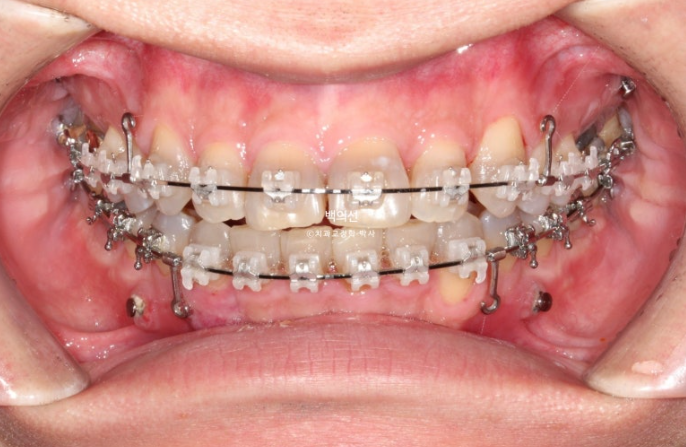

Before the no-prep laminate, we decided to first proceed with non-extraction canine crowding correction using CLIPPY-C.

The space needed to align the crowded teeth was to be obtained by moving the molars backward using the wisdom tooth space.

For this, four orthodontic mini-screws are needed.

After 1 year and 4 months since the start of treatment, orthodontic treatment was finally completed.

Orthodontic treatment for no-prep laminate is a little different from ordinary orthodontic treatment in terms of results. Since the upper front teeth become slightly longer after the no-prep laminate is placed, the bite on the front teeth is intentionally made shallower.

In addition, for no-prep laminate on the lower front teeth, the space between the back surface of the upper teeth and the incisal edge of the lower front teeth needs to be wide.

Only by finishing with these points in mind can true no-prep laminate treatment be possible.